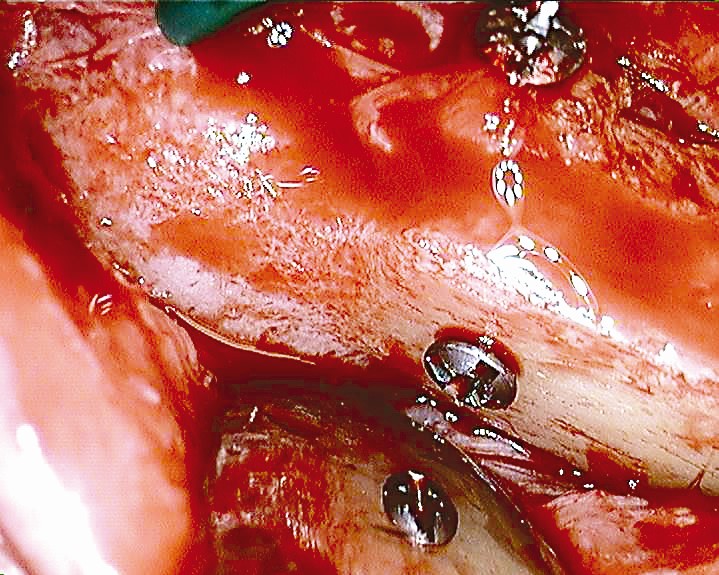

Preparation of a single tooth defect with severely resorbed vestibular wall